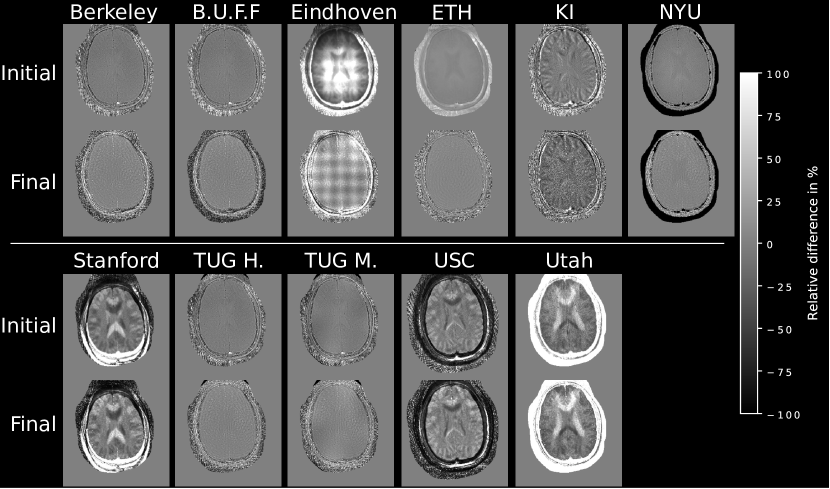

3.2 Differences to Consolidated Implementation

Visually, no major differences to the submissions are visible. Pixel-wise difference plots are shown in Figure 6 and Figure 7. Reconstructions from Eindhoven, KI, USC, Stanford and Utah show some misalignment caused by image center shift, rotation or matrix size differences compared to the reference after cropping to the desired resolution of 300×300300300300{\times}300 pixels. Small intensity variations across the brain are visible in the final step of the TUG M. reconstruction. Reconstructions from Berkeley, B.U.F.F., ETH, NYU and TUG H. show the least deviations to the reference. Visually no difference in the brain tissue can be seen. Initial steps seem to show good agreement if image alignment matches with only minor intensity difference in some submissions. Heart data shows overall more differences, especially in areas of low SNR. The heart itself seems consistent between most reconstructions. At the highest acceleration, differences become more pronounced.

Figure 6: Relative pixel-wise difference of the example reconstruction results to the Python reference implementation. To account for different intensities, all images were normalized prior to the difference operation, however the submissions were not registered in terms of lateral shifts or rotation. Still, most reconstructions do not show substantial structural differences to the reference.

Refer to caption

Figure 7: Relative pixel-wise difference of the example reconstruction results to the Python reference implementation. To account for different intensities, all images were normalized prior to the difference operation. Most reconstructions show similar structural information in the heart itself but differ in low signal areas. With increased acceleration differences become more pronounced.